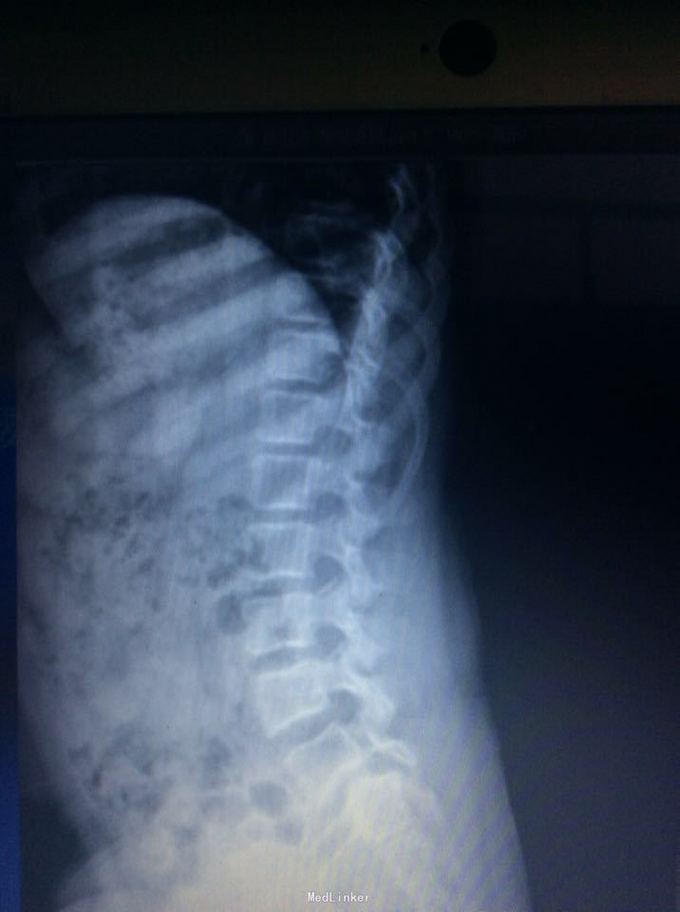

腰椎滑脱

椎体滑脱

9岁,腰痛一年

腰5椎体滑脱ii度 后路椎弓根钉椎间自体髂骨融合